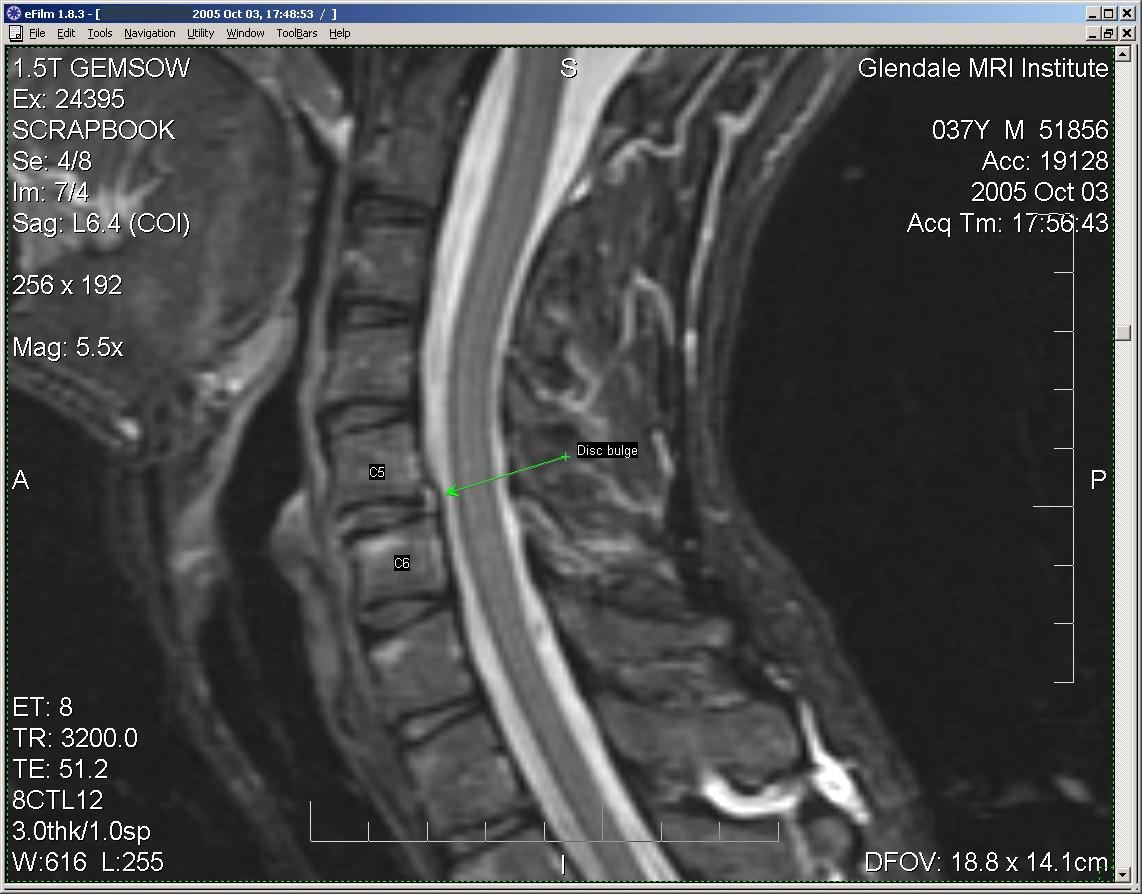

This shows the post-traumatic disc bulge at C5-6. The thin vertical black line that forms the posterior border of the disc is a combination of the disc capsule (aka "annulus") and a key ligament known as the "posterior longitudinal ligament" (PLL). The PLL is a key stabilizer of the vertebral bodies, located at the anterior margin of the bony spinal canal.